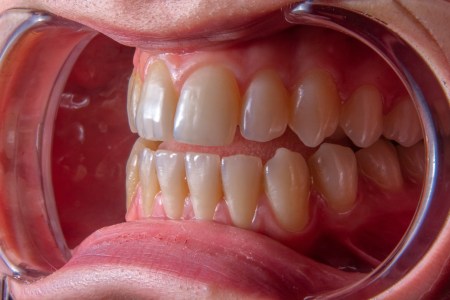

Ortopedija vilica

Ortodoncija je stomatološka grana koja se bavi dijagnostikovanjem, ispravljanjem i lečenjem nepravilnosti vilice i položaja zuba. Cilj je postizanje pravilnog zagrižaja...